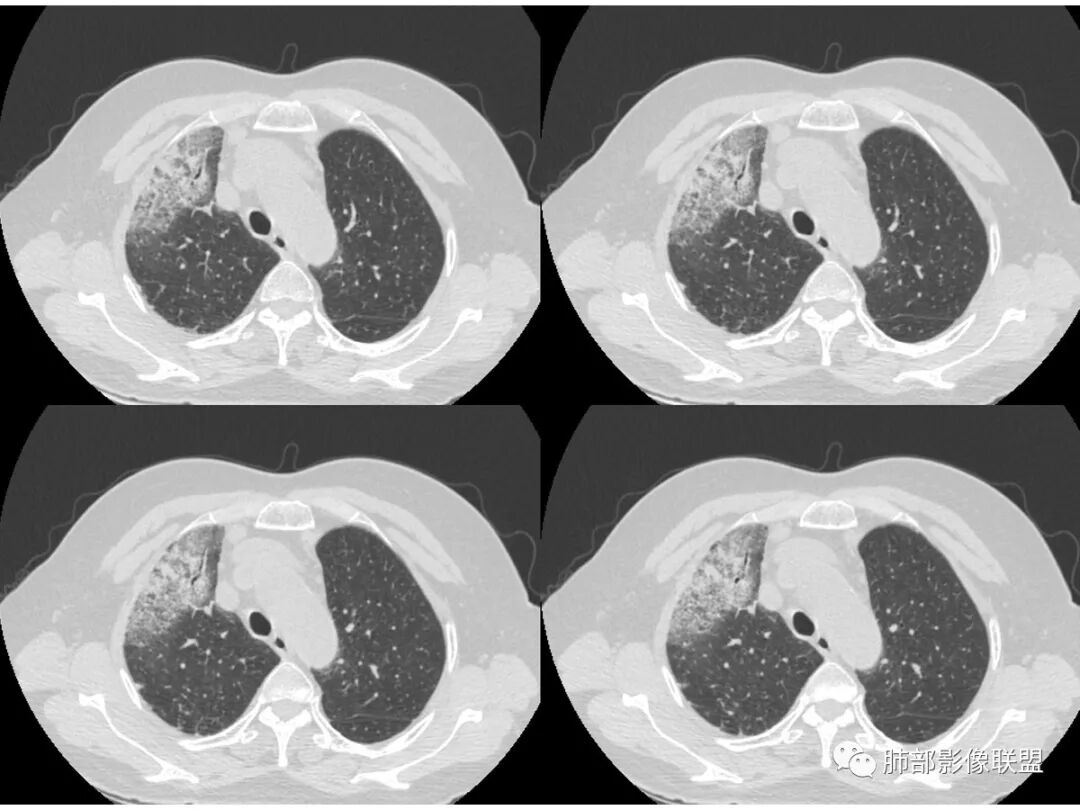

病史老年女,白痰;影像实变,ggo多数边界清,病灶下缘部分不清,枯树枝,支气管近端阻塞、僵硬,病灶跨叶;病灶内空洞,有液平;间质增厚有结节感;肺炎型肺癌大于干酪性肺炎。

右肺上叶、中叶大片实变影,实变影边缘较平直,内部可见一空洞液平,壁光整,实变周围斑片磨玻璃影,考虑感染性病变伴出血!

老年女性,咳白粘液痰;右肺上叶大片实变加GGO,局部膨隆也有收缩,见枯树枝征及坏死,考虑恶性~粘液腺癌,鉴别感染,血象不高。

老年女性,慢性病程,咳嗽伴白色粘液痰,无发热腹痛,糖尿病,白细胞及C反应蛋白不高,血沉快,铁蛋白高。胸部CT,右肺上叶大片状实变伴磨玻璃密度影,边界不清,边缘局部膨隆,叶裂弧形下坠,实变影宽基底与胸膜相贴;右肺下叶前基底段见类似病灶;右肺中叶不张并空洞形成,空洞内见气液平面;综合考虑右肺上叶及下叶肺炎型肺癌,右肺中叶结核。

老年女性,病史1月,右肺上中叶大片状影,跨叶,上叶为主,磨玻璃为主,边界模糊,部分实变,内见空洞影和液气平面,壁光滑,支气管开口狭窄,局部有扩张,右肺门淋巴结钙化,首先考虑感染性病变,结核可能,鉴别粘液腺癌。

患者老年女性,亚急性起病,胸部CT:右肺上叶大片实变,可内见坏死性空洞,可见mGGO,GGO边缘清晰,局部彭隆,内见支气管充气征,可惜没增强,粘液腺癌要考虑,但病灶明显是内朝外不支持,综合考虑结核,建议查痰找抗酸杆菌、气管镜

老年女性,咳白色粘液痰,右肺跨叶大片高密度影,密度不均匀,其内见支气管枯树征,有空洞,边缘部分清楚,叶间裂有下坠膨隆感。考虑粘液腺癌,鉴别干酪性肺炎

老年女性,病史一月,无发热

咳白色粘痰

GGO边界偏清

整体体积缩小,局部占位效应明显

无肺气肿背景,但是局部有空洞或假空洞

中央有间隔

局部支气管有受压狭窄

小叶间隔增厚,重力趋势

还是要考虑癌

常规要抗炎后复查一下